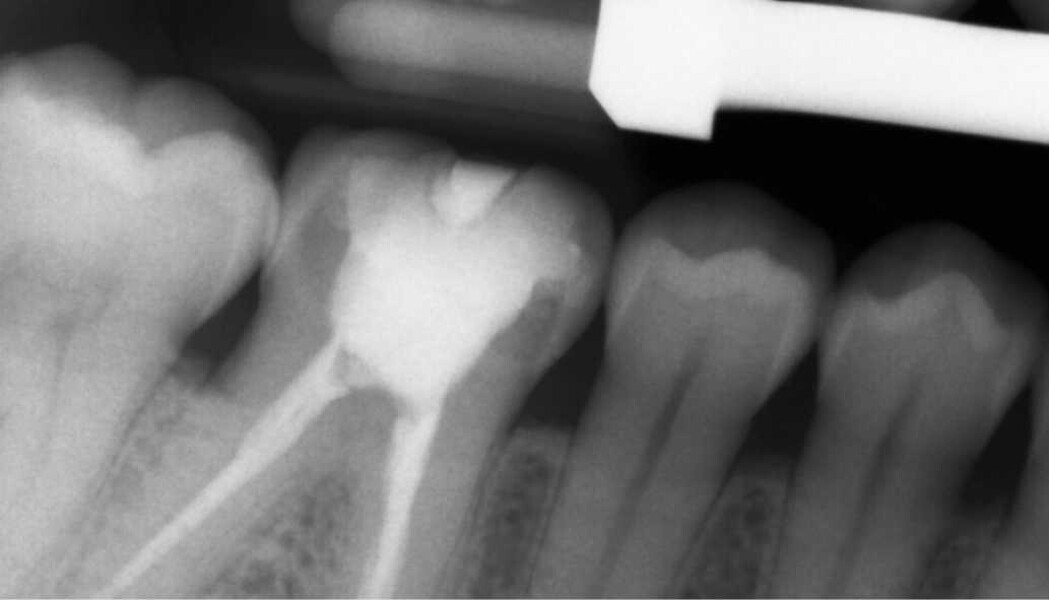

Fig. 1. Situación inicial.